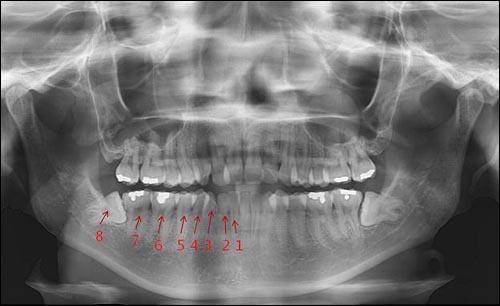

사랑니는 우리 입속에 가장 뒤에 난 어금니를 말하며, 전문용어로 설명해 드리면 제3대구치라고 하며 얼굴을 중심으로 좌우로 8번째 자리하고 있는 치아를 말합니다. 사랑니는 사춘기 이후에 자란다고 합니다. 사춘기에는 여러 가지 감정을 느끼게 되고 그 감정 중 하나가 사랑이라는 감정이지요. 그래서 이 치아를 사랑니라고 부른다고 합니다.

치과 치료를 하면 알 수 있는 것이 치아는 함부로 뽑지 않습니다. 정말 최대한 살려보고 그래도 안 되면 뽑아서 임플란트 등으로 빈자리를 채웁니다. 사랑니는 다른 치아들과 달리 발치를 해야 할 때도 있습니다. 잘 자란 사랑니는 특별한 문제를 일으키지 않아 뽑지 않아도 됩니다. 하지만 대부분의 사랑니는 말썽을 부립니다. 출혈, 염증, 통증 및 악취, 충치 들 여러 가지 문제를 일으킬 확률이 높기 때문에 뽑아야 합니다.